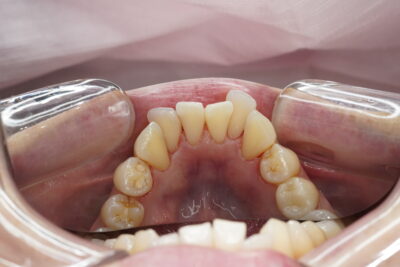

上下の前歯の裏側に着色の付着がみられました

普段お茶とコーヒーをよく飲まれるそうです☕️

エアフロー後🦷✨

綺麗になりました☺️✨

🦷処置内容:歯科衛生士処置(エアフロー)60分